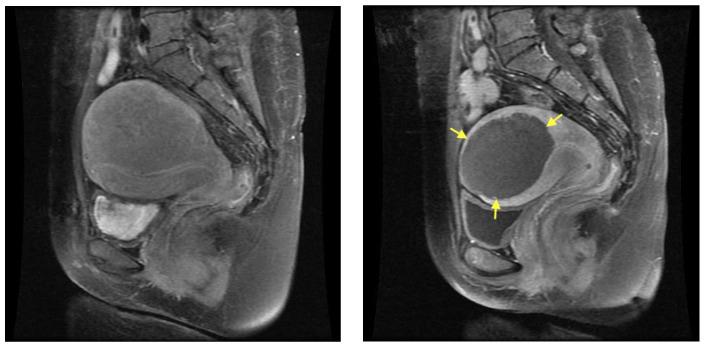

This study evaluated the efficacy and safety of ultrasound-guided high-intensity focused ultrasound (HIFU) in treating symptomatic uterine fibroids and adenomyosis. HIFU treatments performed in premenopausal women with symptomatic uterine fibroids and adenomyosis were analyzed retrospectively. Lesion volume reduction, change in symptoms of menstrual pain, and quality of life were examined. Major and minor complications, together with re-intervention rates, were evaluated. Eighty-one HIFU treatments were performed in seventy-nine premenopausal women. The follow-up period was up to 95 months. A total of 65 women underwent treatment for uterine fibroids and 14 were treated for adenomyosis. For patients with uterine fibroids, the baseline fibroid volume median was 190.1 cm (18.5-1729.4 cm). Fibroid volume was reduced by 50.1% (-26.2-97.8, < 0.0001) at 6 months and 66.9% (-33.7-98.3, < 0.0001) at 12 months after treatment. The modified Uterine Fibroid Symptom and Quality of Life (UFS-QOL) scores had decreased by 43.5% (0-62.5%, < 0.0001) at 6 months and 50% (0-73%, < 0.0001) at 12 months after treatment. In the adenomyosis arm, the median baseline uterine volume was 97.7 cm (43.7-367.4 m3). Uterine volume was reduced by 19.6% (range: 1.2-42.0, = 0.28) at 6 months and 41.9% (18.9-69.2, = 0.04) at 12 months after treatment. UFS-QOL scores were reduced by 38.1% (6-66.7%, < 0.0001) at 6 months and 40% (0-70%, < 0.0001) at 12s month after treatment. Fourteen (21.5%) patients with uterine fibroid and five (35.7%) patients with adenomyosis required subsequent interventions. HIFU provides symptomatic relief to most patients with uterine fibroids and adenomyosis. It is a promising uterus-sparing treatment for patients with these conditions.

本研究评估了超声引导下高强度聚焦超声(HIFU)治疗有症状子宫肌瘤和子宫腺肌病的疗效及安全性。对绝经前有症状子宫肌瘤和子宫腺肌病的女性进行的HIFU治疗进行回顾性分析。检查病灶体积缩小情况、痛经症状变化及生活质量。评估主要和次要并发症以及再次干预率。79名绝经前女性共接受了81次HIFU治疗。随访期长达95个月。共有65名女性接受子宫肌瘤治疗,14名接受子宫腺肌病治疗。对于子宫肌瘤患者,基线肌瘤体积中位数为190.1 cm³(18.5 - 1729.4 cm³)。治疗后6个月肌瘤体积缩小50.1%(-26.2 - 97.8,P < 0.0001),12个月时缩小66.9%(-33.7 - 98.3,P < 0.0001)。改良的子宫肌瘤症状与生活质量(UFS - QOL)评分在治疗后6个月下降了43.5%(0 - 62.5%,P < 0.0001),12个月时下降了50%(0 - 73%,P < 0.0001)。在子宫腺肌病组,基线子宫体积中位数为97.7 cm³(43.7 - 367.4 cm³)。治疗后6个月子宫体积缩小19.6%(范围:1.2 - 42.0,P = 0.28),12个月时缩小41.9%(18.9 - 69.2,P = 0.04)。UFS - QOL评分在治疗后6个月下降了38.1%(6 - 66.7%,P < 0.0001),12个月时下降了40%(0 - 70%,P < 0.0001)。14名(21.5%)子宫肌瘤患者和5名(35.7%)子宫腺肌病患者需要后续干预。HIFU能使大多数子宫肌瘤和子宫腺肌病患者症状缓解。对于患有这些疾病的患者,它是一种有前景的保留子宫的治疗方法。